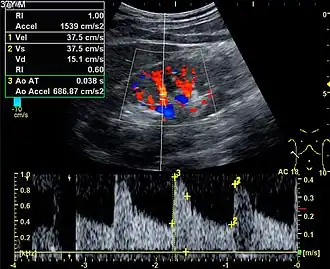

Kidneys

%252C_diastolic_velocity_(Vd)%252C_acceleration_time_(AoAT)%252C_systolic_acceleration_(Ao_Accel)_and_resistive_index_(RI)_of_normal_kidney.jpg)

Doppler ultrasonography is widely used in renal ultrasonography. Renal vessels are easily depicted by the color Doppler technique in order to evaluate perfusion. Applying spectral Doppler to the renal artery and selected interlobular arteries, peak systolic velocities, resistive index, and acceleration curves can be estimated (Figure 4) (e.g., peak systolic velocity of the renal artery above 180 cm/s is a predictor of renal artery stenosis of more than 60%, and a resistive index, which is a calculated from peak systolic and end systolic velocity, above 0.70 is indicative of abnormal renovascular resistance).[12]